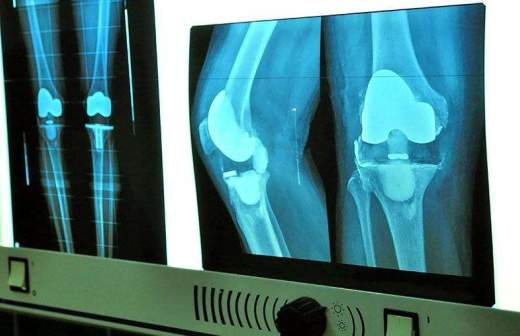

В России появился первый идентичный натуральной кости человека имплант

В России создан первый идентичный натуральной человеческой кости имплант. Об этом «Известиям» рассказали специалисты НИТУ «МИСиС».

Благодаря своим свойствам разработка идеально подходит для протезирования конечностей. При этом нарастающая после операции ткань способна заполнять пористую структуру внутри импланта. Таким образом искусственная кость становится частью организма.

В настоящее время в мире не существует идеального материала для замены костной ткани. Для протезирования используют медицинскую сталь и титан. Несмотря на высокую прочность, они сильно отличаются от человеческой кости.

Кроме того, такие импланты забирают на себя всю нагрузку. Из-за этого собственные ткани организма становятся хрупкими. Поэтому изобретение российских ученых может стать революционным в ортопедии, полагают врачи.

Новый материал уже испытывают на животных, однако ожидать его появления на рынке стоит не ранее чем через 3–4 года. Разработку планируют применять и в ветеринарии для протезирования сломанных лап домашних питомцев.